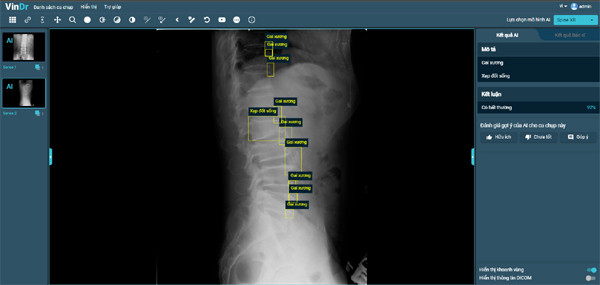

Sau hơn 1 năm tiếp tục nghiên cứu và phát triển, VinBigdata đã tiếp tục phát triển thành công tính năng chẩn đoán X-quang cột sống, phát hiện 6 loại tổn thương phổ biến tại Việt Nam, bao gồm: gai xương; hẹp khe đĩa đệm; vật liệu phẫu thuật; hẹp lỗ tiếp hợp; trượt đốt sống và xẹp đốt sống với độ chính xác khoảng 90%.